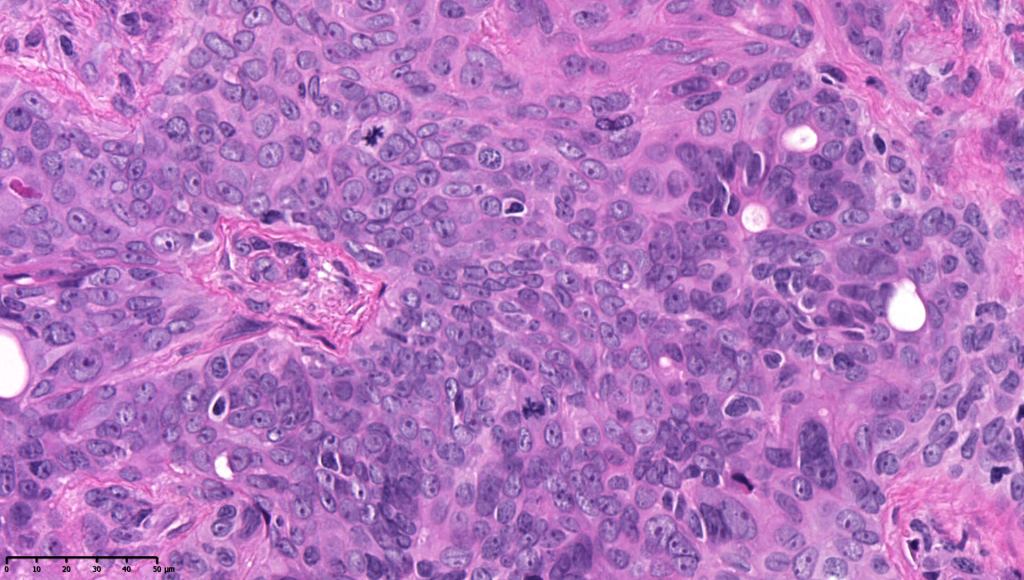

•In poroma, a dermal-centric tumor is associated with epidermal origin/continuity & is composed of small cells with vesical nuclei.

•Desmosomes often prominent

•No peripheral palisading or retraction artifact

•Generally few mitoses but occasionally can be conspicuous. In the absence of other features of porocarcinoma, this should not be taken as necessarily implying maligant potential unless other worrying features sre also present (see case below)

•No pleomorphism or abnormal mitoses

•No lymphovascular involvement or perineural infiltration